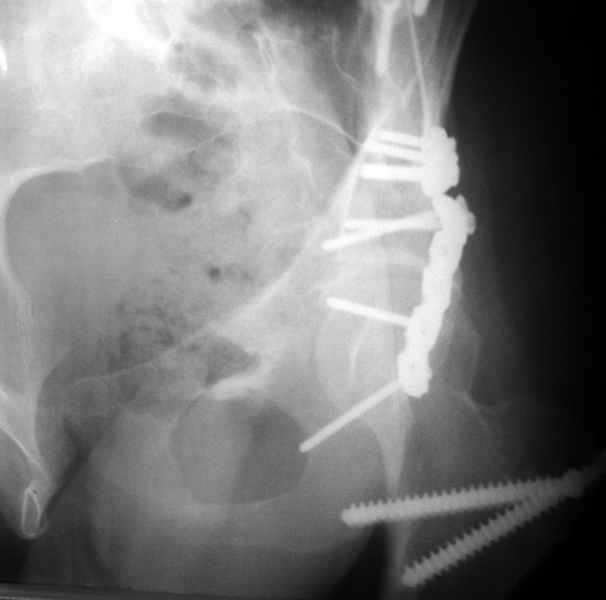

Посылаю схемы и 3D реконструкцию подобного повреждения. Называется он полным высоким двухколонным переломом вертлужной впадины, а "переломы крыла и тела подвздошной кости" входят в это понятие.

Вариантов остеосинтеза много (можно и не оперировть, т.к. конгруентность при таких переломах как правило сохраняется)

1 закрытая репозиция аппаратом + фиксация через проколы винтами

2 закрытая репозиция передней колонны + открытая задней колонны из задне-неружного доступа

3 открытая репозиция передней колонны из подвздошнго доступа + открытая задней колонны из задне-наружного доступа

4 открытая репозиция из илиоингвинального доступа

5 открытая репозиция из Y образного доступа

Я бы ориентировался на Y образный доступ

или из двух если есть сомнения в целостности задних отделов крыла.

прикладываю схему доступа и случай.

Одним задне наружным переднюю колонну не достать, а илио-ингвинальный более сложный не позволяет контролировать суставную поверхность и трудно управлять задней колонной.